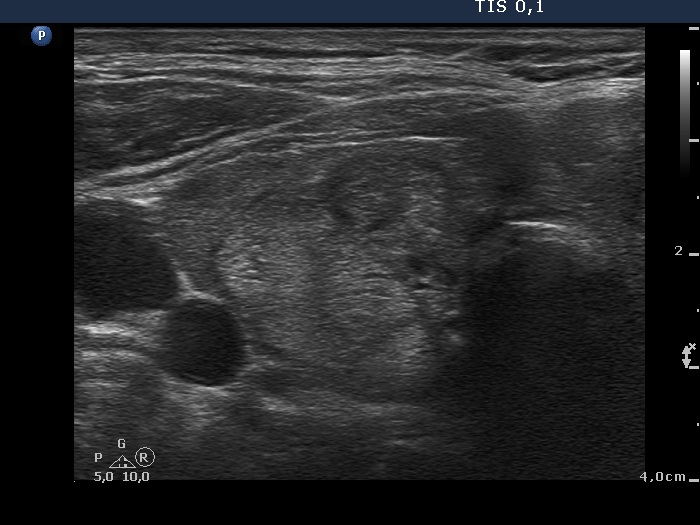

Ultrasonography. The thyroid was minimally hypoechogenic and had multiple discrete lesions which were mostly echonormal. The thyroid had a pseudonodular pattern. There were several hypoechogenic discrete areas.